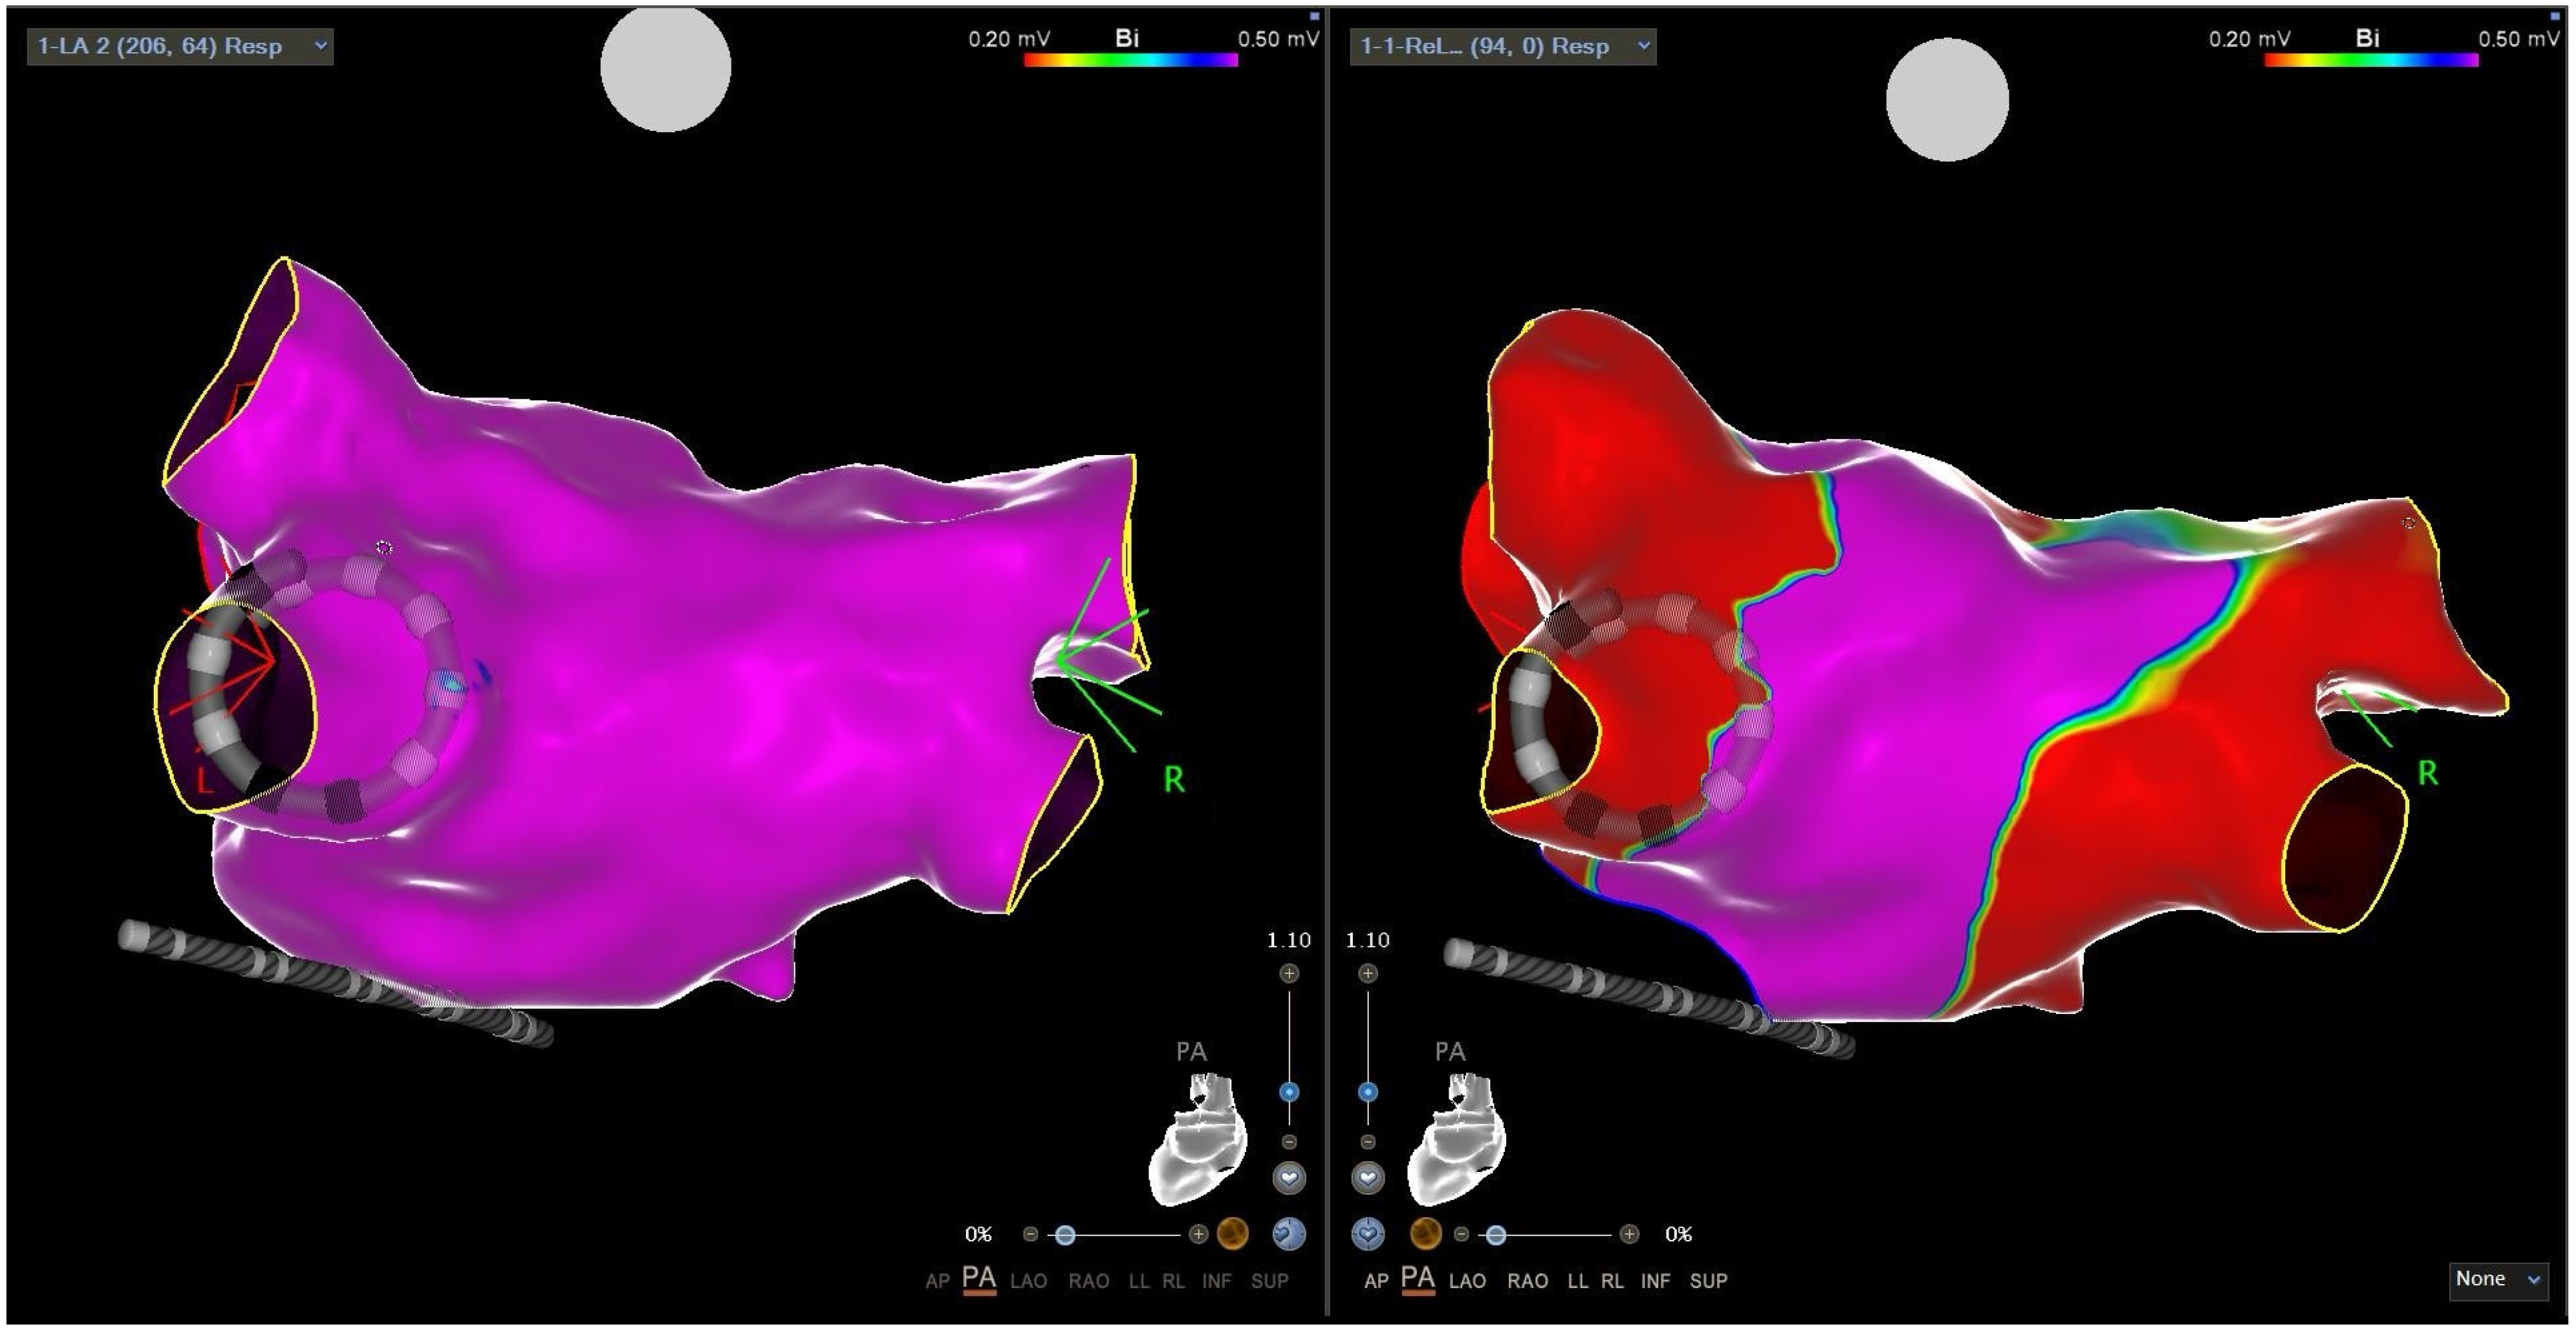

2.3. Intracardiac Echocardiography and CARTOSOUNDFAM MAP Module

2.4.1. Mapping Phase in ICE-Guided Cohort

2.4.2. Mapping Phase in Non-ICE-Guided Cohort